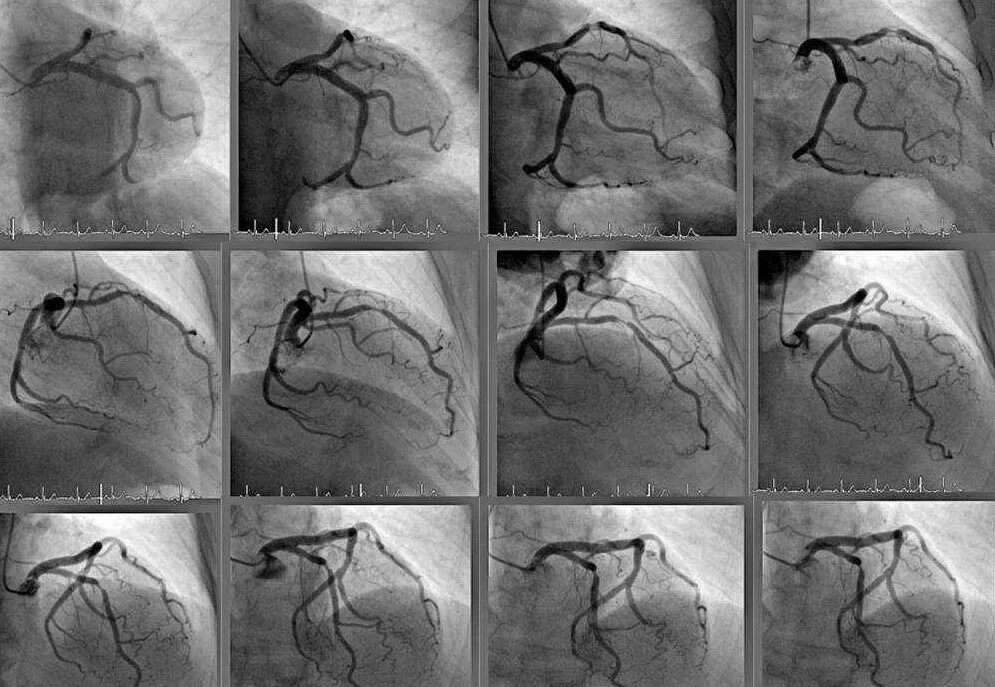

Стенты мрт